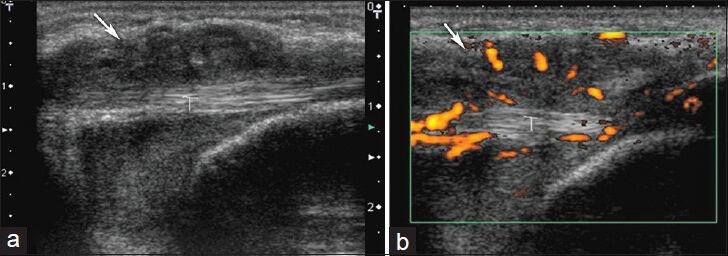

Giant cell tumors of the tendon sheath are the second most common mass in the hand after ganglion cysts. They tend to appear on the volar side of the fingers. On ultrasound, they appear as hypoechoic masses adjacent to joints and are highly vascular structures on Doppler ultrasound.